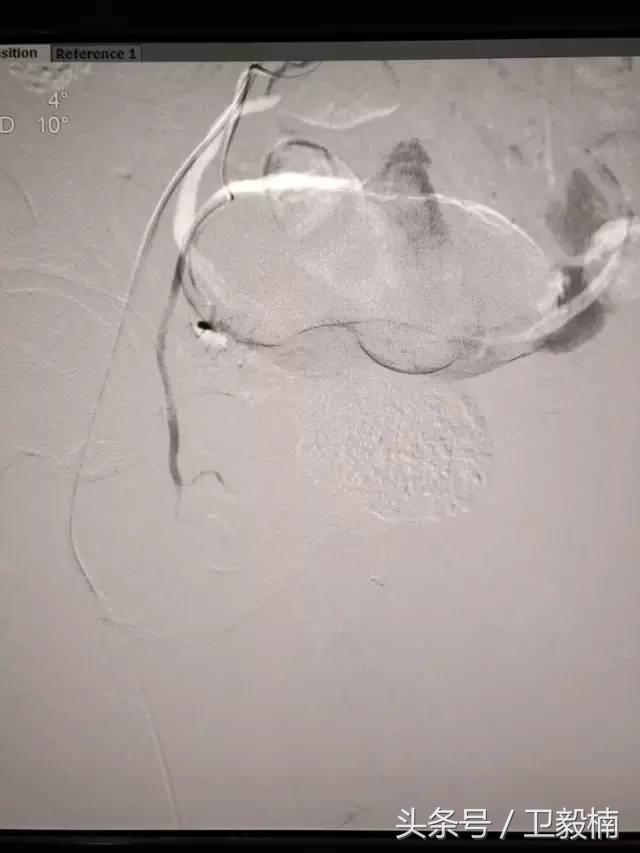

2、经导管血管栓塞法(Transcatheter embolization)

经原血管造影的导管或特制的导管,将栓塞物送至靶血管内,一是治疗内出血如外伤性脏器出血、溃疡病、肿瘤或原因未明的脏器出血。另一是用栓塞法治疗肿瘤,因肿瘤循环部分或全部被栓塞物阻断,以达控制肿瘤之生长,或作为手术切除的一种治疗手段;亦可用于非手术脏器切除,例如注射栓塞物质于脾动脉分支内,即部分性脾栓塞,以治疗脾功亢进,同时不影响脾脏的免疫功能。

常用的栓塞物质如自体血凝块、明胶海绵、无水酒精、聚乙烯醇、液体硅酮、不锈钢圈、金属或塑料小球及中药白芨等。